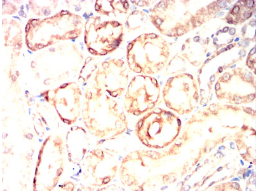

TPSAB1 Mouse Monoclonal antibody[6B611]

Tryptases comprise a family of trypsin-like serine proteases, the peptidase family S1. Tryptases are enzymatically active only as heparin-stabilized tetramers, and they are resistant to all known endogenous proteinase inhibitors. Several tryptase genes are clustered on chromosome 16p13.3. These genes are characterized by several distinct features. They have a highly conserved 3' UTR and contain tandem repeat sequences at the 5' flank and 3' UTR which are thought to play a role in regulation of the mRNA stability. These genes have an intron immediately upstream of the initiator Met codon, which separates the site of transcription initiation from protein coding sequence. This feature is characteristic of tryptases but is unusual in other genes. The alleles of this gene exhibit an unusual amount of sequence variation, such that the alleles were once thought to represent two separate genes, alpha and beta 1. Beta tryptases appear to be the main isoenzymes expressed in mast cells; whereas in basophils, alpha tryptases predominate. Tryptases have been implicated as mediators in the pathogenesis of asthma and other allergic and inflammatory disorders.

Species Reactivity:   Human, Rat

IHC    1/200 - 1/1000